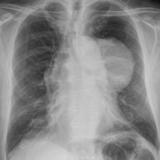

Case 9 Thymoma PA

Date: 04/04/2010

Views: 3176